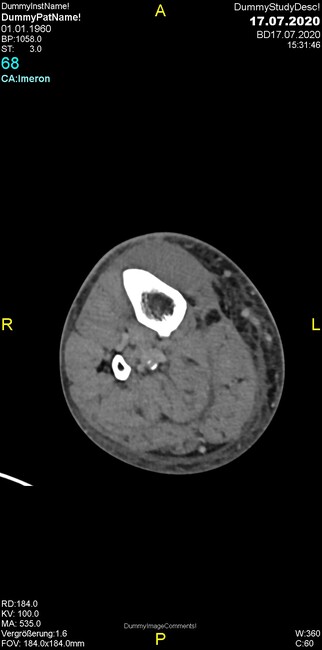

Um welche Modalitäten handelt es sich?

- Röntgen p.a. und lateral, CT coronar Knochenfenster, CT axial Weichgewebsfenster

Was fällt in der Projektionsradiographie auf?

- Verdichtung im Recessus suprapatellaris

- Aufhellungslinie in Projektion auf die Femurkondylen

- Erhöhter tibialer Slope

- Hypertransparenz tibial

- Subluxationsstellung im Kniegelenk

Was trifft auf den Befund zu?

- Der Befund beschränkt sich auf den Knochen.

- Es besteht hochakuter Handlungsbedarf.

- Der Befund ist tendenziell benigne.

- Der Befund ist tendenziell maligne.

- Der Befund weist einen Zusammenhang zum Patientenalter auf.

Was fällt in der CT im Knochenfenster auf?

- Mediale Gelenkspaltverschmälerung

- Dezente Erosion der fibulären Kortikalis

- Frakturspalt der lateralen Tibiametaphyse

- Weichgewebskalzifikationen lateral angrenzend an den Gelenkspalt

- Osteolyse der Tibiametaphyse unter Beteiligung der Kortikalis

Was kommt differentialdiagnostisch in Frage?

- Kompartmentsyndrom

- Osteomyelitis mit Weichgewebsanteil

- Metastase mit pathologischer Fraktur

- Rheumatoide Athritis

- Posttraumatische Verletzung